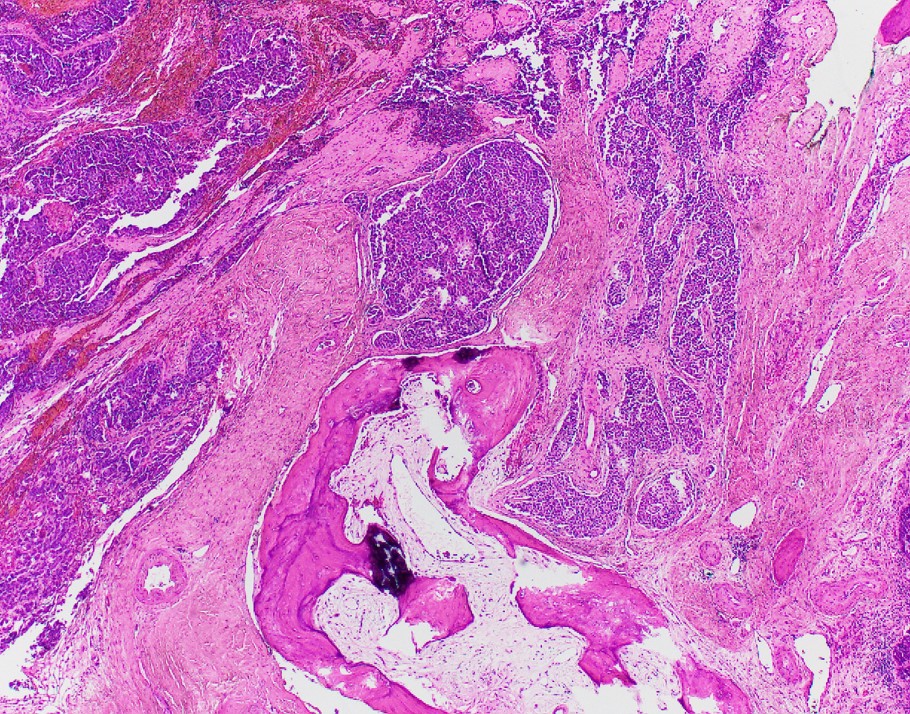

Explanation: INI-1 (SMARCB1)-deficient sinonasal carcinoma, currently listed as a subtype of sinonasal undifferentiated carcinoma (SNUC) in the current WHO Classification of Head and Neck Tumors, is a poorly differentiated sinonasal carcinoma defined by loss of nuclear INI-1 expression due to SMARCB1 deletion (1). Histologically, they have a definitive (adeno)carcinoma appearance unlike other INI-1-deficient tumors such as epithelioid sarcoma and atypical teratoid/rhabdoid tumor. INI-1-deficient sinonasal carcinoma shows islands of eosinophilic/oncocytoid and plasmacytoid carcinoma cells with variable glandular differentiation to include focal intracellular/intraluminal mucin production, and may also show a basaloid appearance (2). INI-1 (SMARCB1)-deficient sinonasal carcinoma typically shows expression of CK7. In one report 3 of 10 showed p40 expression, 4 of 12 examples showed CDX2 expression, and 3 of 12 showed CK20 expression (3). Variable/weak expression of neuroendocrine markers has been described. INI-1 (SMARCB1)-deficient sinonasal carcinoma is negative for high-risk HPV and EBV and is negative for S100 protein expression.

The differential diagnosis of INI-1 (SMARCB1)-deficient sinonasal carcinoma includes high-grade non-intestinal sinonasal adenocarcinoma, myoepithelial carcinoma, nonkeratinizing squamous cell carcinoma, mucosal melanoma, etc. All of the entities in the differential diagnosis, except a proportion of myoepithelial carcinomas, retain INI-1 expression. Myoepithelial carcinoma, unlike INI-1 (SMARCB1)-deficient sinonasal carcinoma, should express S100 protein and other myoepithelial markers (3). Recently the morphologic spectrum of INI-1 (SMARCB1)-deficient sinonasal carcinomas has been expanded to included examples with yolk-sac-like areas that have also shown limited glypican-3, SALL4, and HepPar-1 expression, adding germ cell tumor and metastatic hepatocellular carcinoma to the differential diagnosis (3).